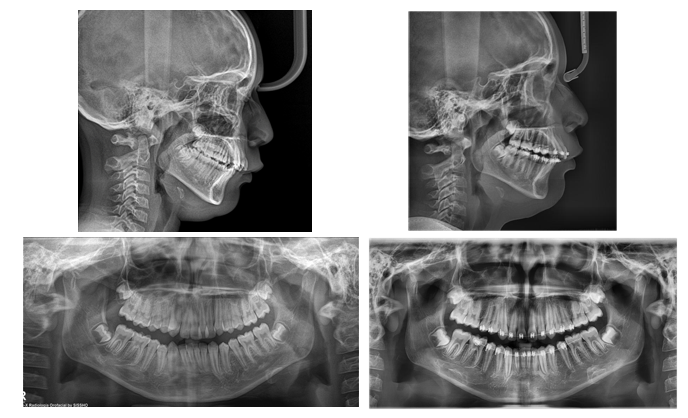

Comments

With disjunction, orthopedic expansion is performed to separate the midpalatal suture by applying forces between 3 and 10 ounces against the lateral sectors of the upper jaw. For each millimeter of posterior expansion, 0.7 mm of arch length is obtained.7 The importance of these disjunctors lies in the fact that they make it possible to correct, without surgical intervention, the contractions of the transverse diameter of the upper arch, which are related to a skeletal base defect. These can often be found associated with class I, II or III malocclusions. The use of the Hyrax expander appliance has the advantage of being more hygienic and comfortable than those with extensions or acrylic plates, besides the fact that results can be seen within days. The effectiveness of this screw in rapid maxillary expansion was demonstrated, as it contributed to improve facial esthetics and the patient's smile. Rapid maxillary expansion performed with a Hyrax type disjunctor in a patient in stage CS2 has a high probability of success. Undoubtedly, a spontaneous repositioning of the mandible to a more anterior position was obtained and changes were observed in the nostrils which were compressed and are now permeable, contributing to better breathing and cerebral oxygenation in the patient (Figure 6 & 7).

Figure 6 Comparative radiographic analysis.